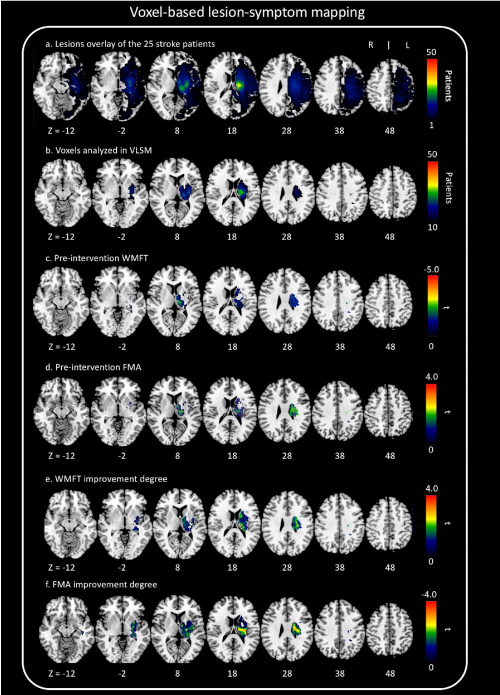

Structural images were preprocessed using Statistical Parametric Mapping software (SPM8: Wellcome Trust Center for Neuroimaging). The images were spatially normalized into the standard Montreal Neurological Institute (MNI) space using a unified segmentation algorithm optimized for use in patients with local brain lesions. Seghier, et al. demonstrated the utility of this procedure using real and artificial lesions [22]. Their analyses showed high sensitivity for detecting and delineating brain lesions with different sizes and textures and at different locations [22]. Their approach has important implications on the generation of lesion overlap maps for a given population and subsequent assessment of lesion-deficit mappings. The unified segmentation algorithm is a generative model that combines tissue segmentation, bias correction, and spatial normalization [22]. Although this algorithm was developed for use with brain images from normal subjects’ brains, in 3D-T1WI images from patients, it outperforms the previous “gold standard,” cost-function masking [23]. The lesion in the images from each patient was automatically identified using a modified unified segmentation algorithm and an outlier detection algorithm [24] set at default parameters. Accuracy of lesion delineation was visually verified in each slice to confirm the possibility and extent of automatic lesion identification and spatial normalization. Representative raw and lesion segmentation overlay images are depicted in Figure 1. These normalized lesions were subjected to statistical mapping analysis using VLSM algorithms implemented in the MRIcron NPM analyzing package (Columbia, SC, USA) [25] to determine brain areas where damage related to improvement in motor function had occurred. Pre-intervention WMFT scores and a change in these scores were used in the VLSM analysis. We used the nonparametric Brunner–Munzel test [26] to statistically compare voxel-based data, as present in NPM and MRIcron software [27]. Brunner–Munzel tests on continuous pre-intervention WMFT and FMA scores and changes in the WMFT score were performed on a voxel-by-voxel basis to compare performance in patients with a lesion compared with that in patients without a lesion. For appropriate Brunner–Munzel statistics, only voxels affected in at least 10 patients were tested [28]. To correct for multiple comparisons, we used a permutation-based family-wise error (FWE) correction with 1000 permutations with a correction threshold of 5%. The results of Brunner–Munzel tests were color-coded and mapped on the MNI brain template by the software [27]. In this study, we also adopted an Atlas-based analysis. The anatomical localization of significantly affected regions, as identified by VLSM, was based on the Anatomical Automatic Labeling (AAL) Atlas and the Johns Hopkins University (JHU) Atlas. Briefly, the brain was parcellated based on anatomical labeling, including gray and white matter.

Figure 1. Raw image and lesion segmentation overlay

Representative images (raw image and lesion segmentation overlay) from study subjects. Accuracy of lesion delineation was visually verified for each slice to confirm plausibility and extent of automatic lesion identification and spatial normalization.